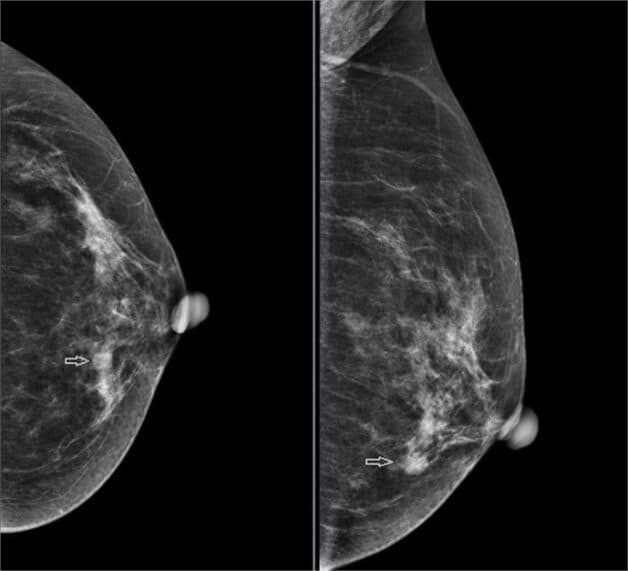

Trong khi phụ nữ có mật độ tuyến vú đặc không có vấn đề sức khỏe, nhưng điều này có thể tạo ra khó khăn trong việc phát hiện tổn thương trên vú. Trên phim chụp X-quang tuyến vú, mô vú dày đặc xuất hiện như một vùng trắng đặc, làm cho việc nhận biết các dấu hiệu của ung thư vú trở nên khó khăn.

Hình ảnh mô tuyến vú đặc

Mô vú dày đặc, bao gồm cả mô xơ và tuyến, xuất hiện màu trắng trên phim chụp X-quang tuyến vú. Điều này tạo nên một bức tranh màu sắc đồng đều giữa mô dày và các khối u, cũng màu trắng. Kết quả là, các khối u và ung thư có thể trở nên khó nhìn thấy và dễ bị che giấu trong mô vú dày đặc. Trong khi mô mỡ thường trở nên đen khi chụp X-quang, làm nổi bật hơn các khối u màu trắng.